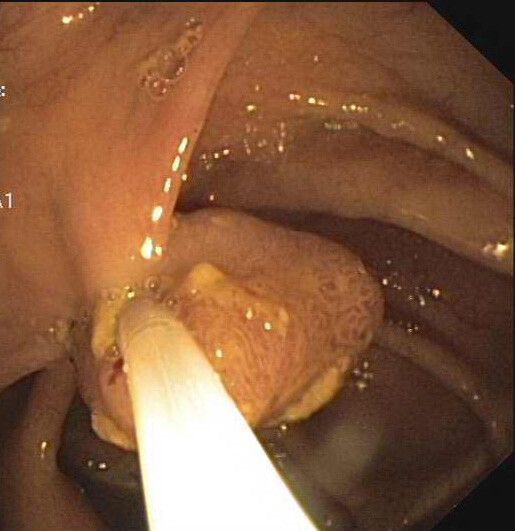

Einig sind sich Experten zumindest über den ökonomischen Nutzen des Programms. In Vorarlberg lassen sich laut Ärztekammerstudie nach zehn Jahren 15 Millionen Euro einsparen, danach jährlich sechs Millionen. Die Daten auf Österreich hochgerechnet, würde die Darmvorsorge nach zehn Jahren eine Ersparnis von 375 Millionen Euro bringen. Anschließend wären es jährlich immer noch 137 Millionen Euro. Die Behandlung eines fortgeschrittenen Darmkarzinoms kostet durchschnittlich 235.000 Euro. In Vorarlberg haben zwischen 2007 und 2021 bereits 52.300 Personen ab 50 Jahren eine Koloskopie-Vorsorge in Anspruch genommen. In 55 Prozent der Fälle (29.000) erbrachte die Untersuchung einen Normalbefund, bei 23.000 Personen wurden Polypen festgestellt, bei 966 von ihnen zeigten die Polypen bereits maligne Veränderungen, bei 889 Personen befanden sie sich noch im Vor- bzw. Frühstadium. Die Polypen wurden entfernt, denn sie sind der Nährboden, auf dem Krebszellen gedeihen können.

Hohe Heilungschance

In den Vorstadien besteht eine hundertprozentige Heilungschance, später sinkt das Überleben drastisch. Wird die Darmspiegelung alle zehn Jahre durchgeführt, ist eine Reduktion der Sterblichkeit um 70 Prozent möglich. „Die Evidenz des Programms ist also belegt“, betont der ÖGK-Landesstellenvorsitzende. Erfreulicherweise habe das Gesundheitsministerium rasch auf die Praevenire-Petition, deren Impulsgeber Manfred Brunner übrigens war, mit einem Gesprächstermin reagiert. Was dabei herauskommt, muss sich jedoch erst weisen.